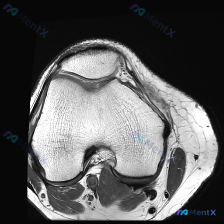

问题核心:用户提供单张膝关节轴位T1加权MRI图像,询问图像中是否存在软骨异常。

- 扫描层面为膝关节轴位,涵盖股骨远端滑车区与髌骨

- 股骨髁、髌骨骨髓信号正常(T1序列弥漫高信号符合正常表现),皮质骨连续清晰,无侵蚀灶或骨缺损

- 髌股关节软骨层形态可,关节间隙无狭窄,软骨下骨表面无明显信号异常中断或局灶变薄

- 髌韧带及周围软组织无肿胀、信号异常,关节间隙无明显积液,滑膜无增厚

- 此层面未包含交叉韧带、半月板等深部结构

针对「软骨异常」的提问,基于现有图像的客观结论是:这张轴位T1图像上未见明确的软骨异常征象,髌骨和股骨滑车软骨的形态、厚度、信号都没有发现支持显著软骨损伤、缺损或软化的直接证据。